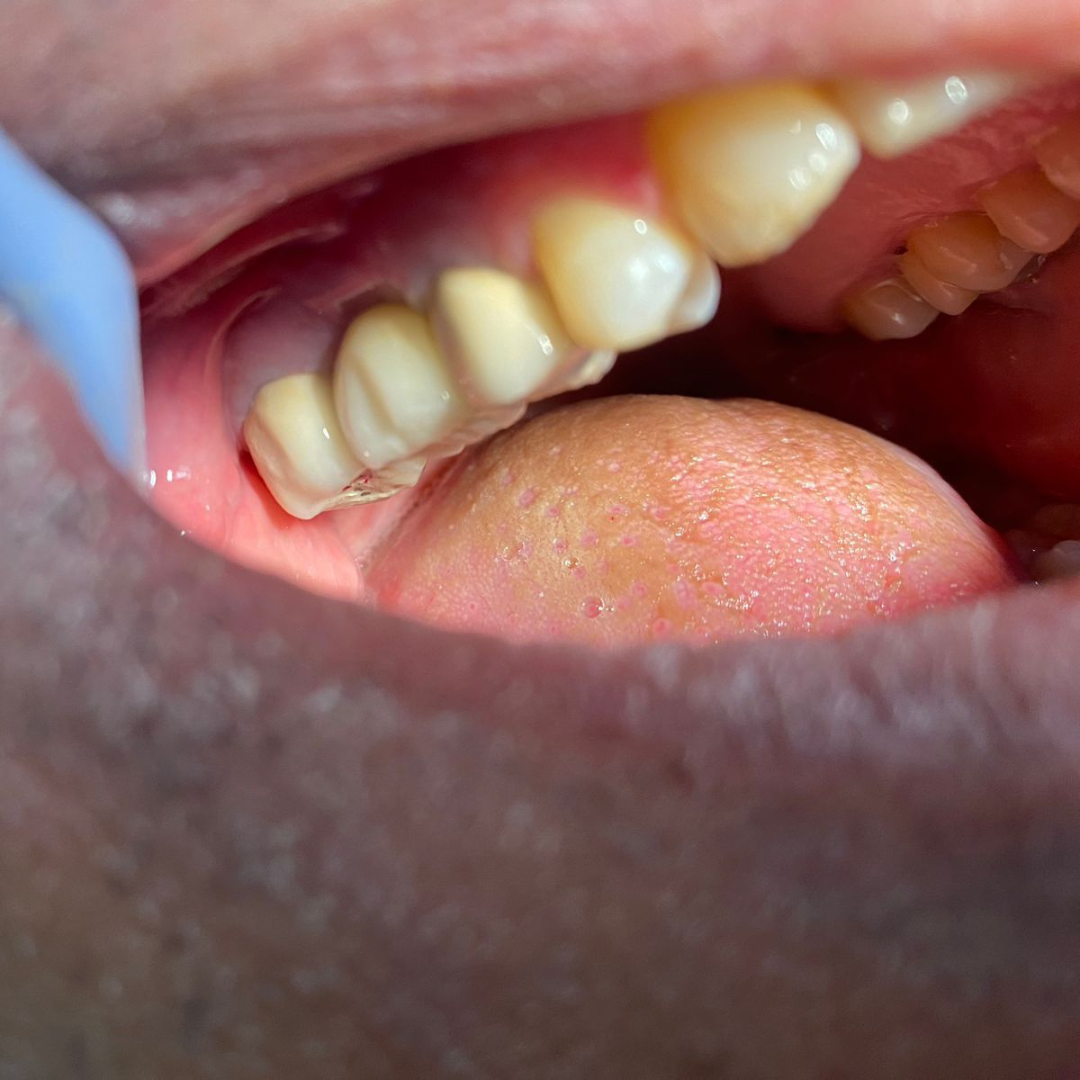

Throughout my studies, I immersed myself in learning, not just from books, but through hands-on experience at a local dental clinic. I spent countless hours there, treating patients and gaining invaluable practical skills. The joy and relief I saw in their eyes after each session were my greatest rewards. My humility and dedication earned me the love and respect of everyone around me.